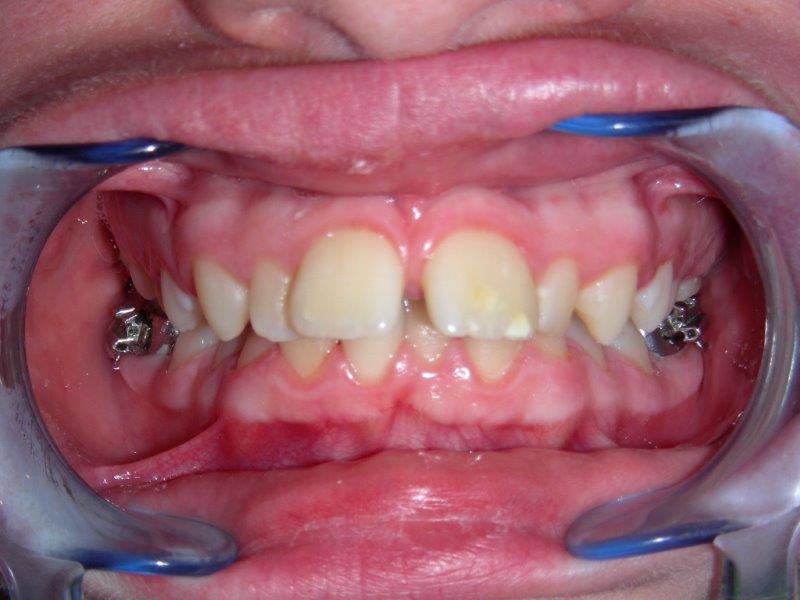

sobremordida1 SOBREMORDIDA, las paletas de arriba recubren completamente las de abajo. Las paletas inferiores pueden llegar a morder el paladar.

Se puede utilizar enganches (o brackets) que se pegan en las caras de los dientes para desplazarlos haciéndoles deslizarse sobre arcos, hasta obtener una oclusión correcta y estable.

Son los aparatos más utilizados y los más eficaces ya que la fuerza que se ejerce sobre las piezas dentales son constantes y muy precisas (cada diente se desplaza individualmente). Se utilizan diversos enganches, brackets, que se pegan sobre cada diente así como arcos para los desplazamientos dentales.

• Brackets metálicos (visibles)

• Brackets estéticos del color de los dientes.

• Existen también, brackets metálicos pegados sobre la cara interna de los dientes, y que no se ven.